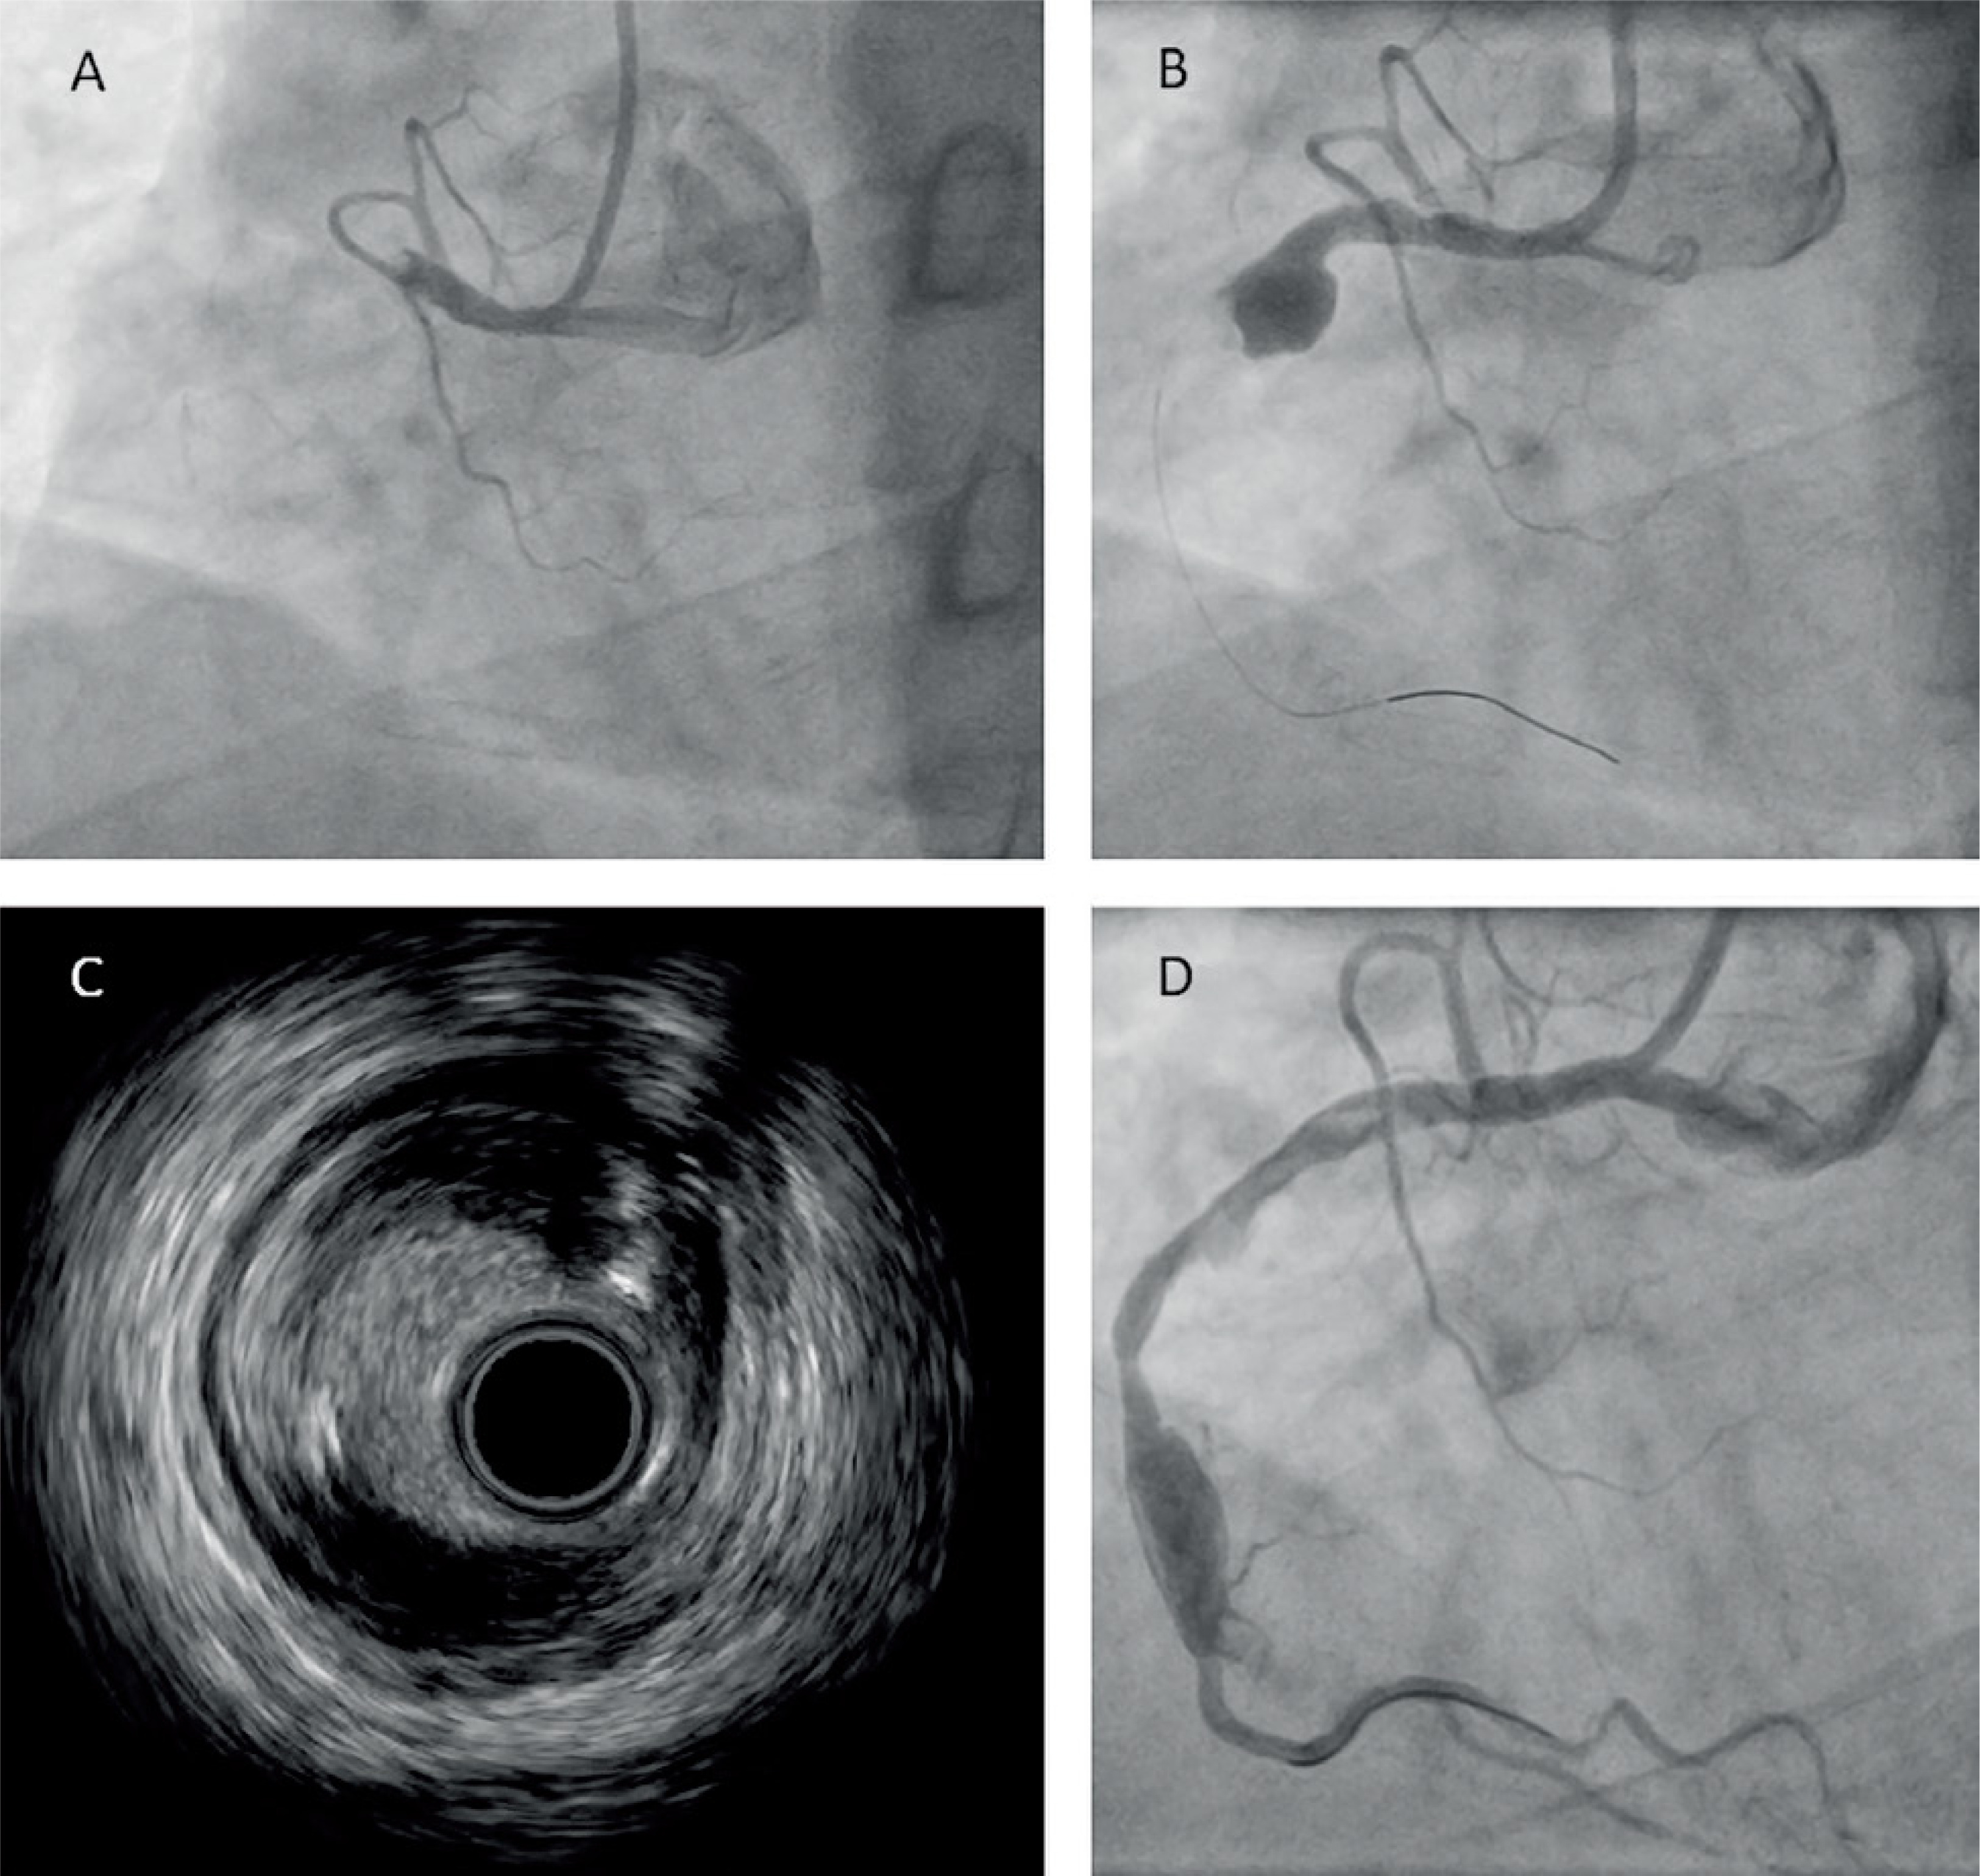

A 53-year-old male patient with multimorbidity – hypertension, hyperlipidemia, type 2 diabetes, multivessel coronary disease – and a history of multiple percutaneous coronary interventions (PCIs), presenting with non-ST-elevation myocardial infarction, was admitted to the cardiology department. Coronary angiography showed total occlusion of the proximal right coronary artery (RCA) (Figure 1 A), with developed collateral circulation. Echocardiography on admission showed slightly decreased left ventricular ejection fraction (LVEF) of 45–50%.

Figure 1

A – Angiographic image of the right coronary artery (RCA) before the first stage of percutaneous coronary intervention (PCI). B – Angiographic image of the RCA after the primary PCI; large aneurysm visible (arrow). C – Intravascular ultrasound (IVUS) during the second stage of PCI. D – Angiographic image of the RCA after the mechanical thrombectomy (MT)

Primary PCI of the RCA with subsequent 7F manual thrombectomy (iVascular, Spain) was performed. The aspirate contained multiple fragments of thrombus. Control coronary angiography revealed a large aneurysm with a 12 mm diameter and a massive thrombus in its distal part, occluding the middle and distal segments of the RCA (Figure 1 B). Due to the clinical image and very low probability of restoring vessel patency, the patient was managed conservatively with dual antiplatelet therapy (including ticagrelor) and anticoagulation with low molecular weight heparin.

Seven days later, follow-up angiography, performed due to exertional angina, revealed total occlusion of the RCA, and another PCI, this time with an MT IndigoCath RX 6F system (Penumbra, USA), was performed under intravascular ultrasound (IVUS) guidance (Figure 1 C). Multiple passages of thrombectomy were performed with removal of abundant debris, restoring a TIMI 3 flow (Figure 1 D). Next, several balloon inflations (2.5 × 20 mm to 20 atm, 3.0 × 15 mm to 16 atm), including prolonged inflation of a drug-eluting balloon (DEB) 3.5 × 30 mm, were performed. The posterior descending branch of the RCA remained occluded, as it turned out to be a chronic total occlusion. The patient was started on further conservative treatment and discharged home in a good overall condition.